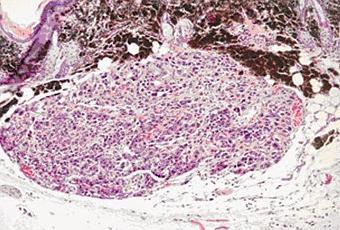

Sur cette coupe histologique d'un mélanome, les cellules tumorales commencent à envahir le derme

Source iconographique et légendaire: http://www2.cnrs.fr/presse/communique/1223.htm